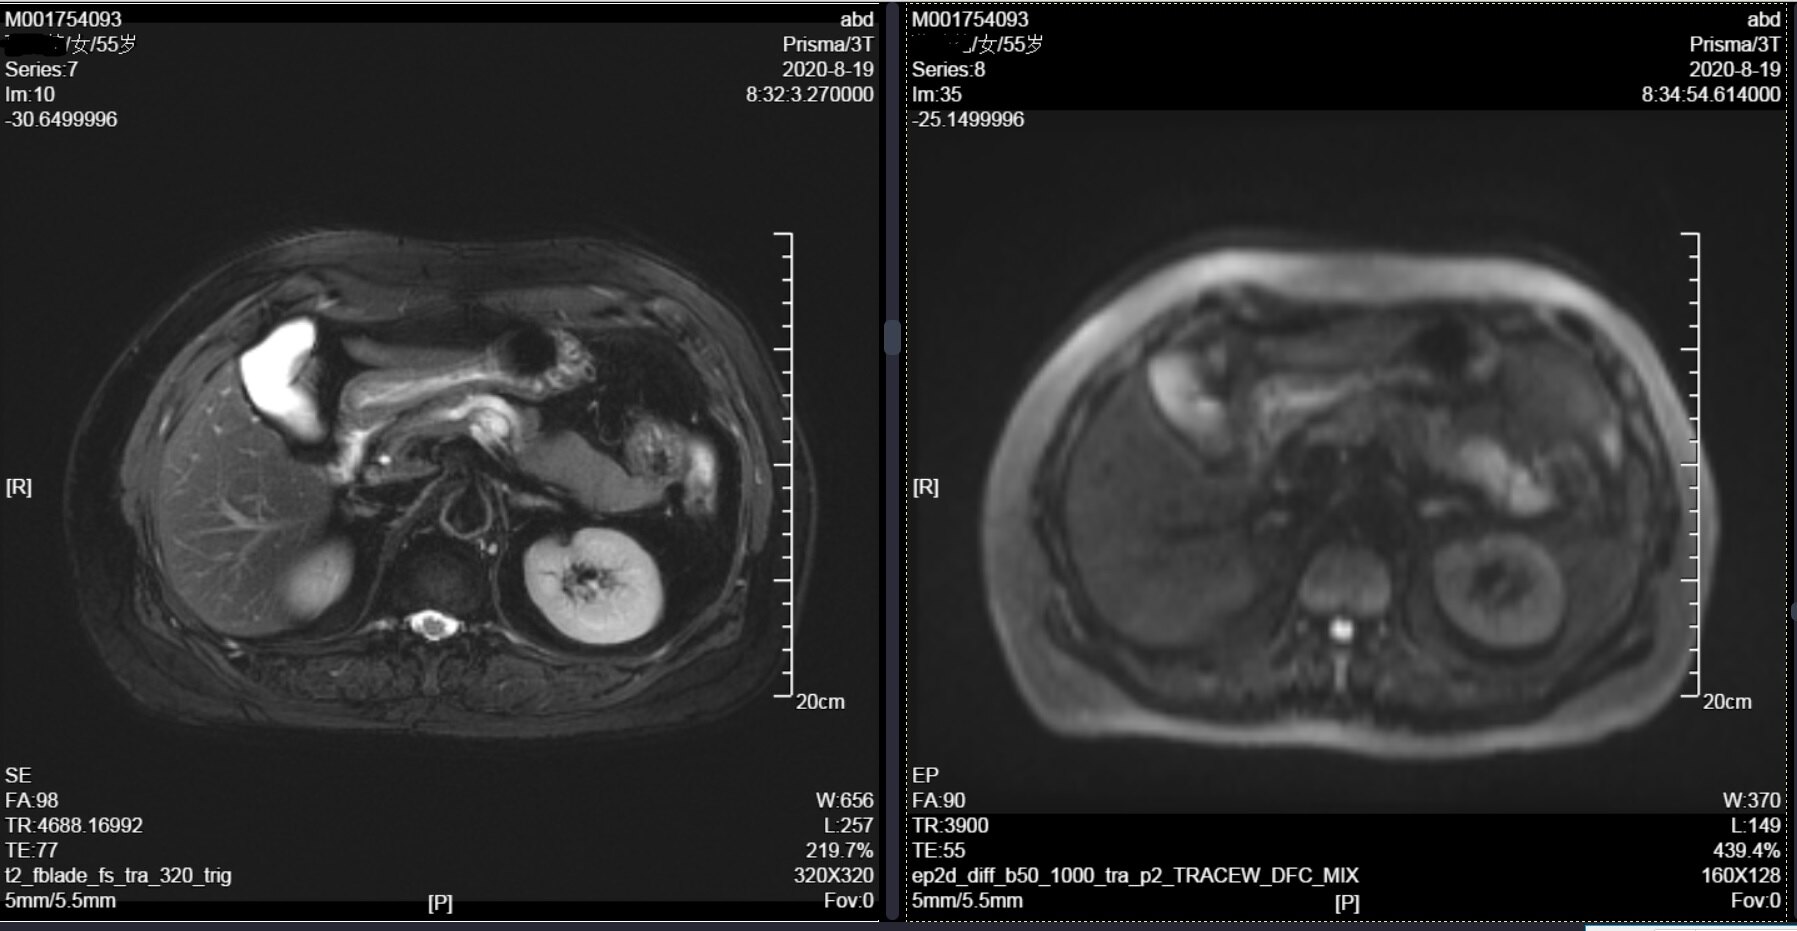

2、患者于2年前查体发现胰腺囊肿,未予诊治,2月前体检复查行腹部CT示:胰管扩张,胰体部稍低密度灶导管内乳头状粘液瘤?患者自诉无不适,无腹痛、腹胀、恶心、呕吐、黄疸、头晕、乏力,无发热,无尿频、尿急、尿痛。1月后行上腹部增强MRI+MRCP示:胰管扩张,胰体部多房囊性灶,IPMN可能性大。为行进一步诊治收入院,患者自起病来,精神状态良好,体力情况良好,睡眠食欲良好,体重无明显变化,大小便正常;

4、外院腹部增强MRI+MRCP:胰管扩张,胰体部多房囊性灶,胰腺导管内乳头状黏液性肿瘤可能性大;肝内多发囊肿;左侧肾上腺结节样增粗,小腺瘤可能。

CT和核磁都发现囊肿与主胰管相通,并且发现主胰管扩张、在胰腺体尾部多发囊肿,提示胰腺体尾部多发病变。同时疾病较2年前进展,说明胰腺导管内乳头状黏液性肿瘤在慢慢的发生改变,有必要在癌变前手术,切除胰腺体尾部,阻止癌变。同时目前肿瘤偏良性,希望能够尽量保留住脾脏,减少术后血栓、免疫功能受损等等影响。